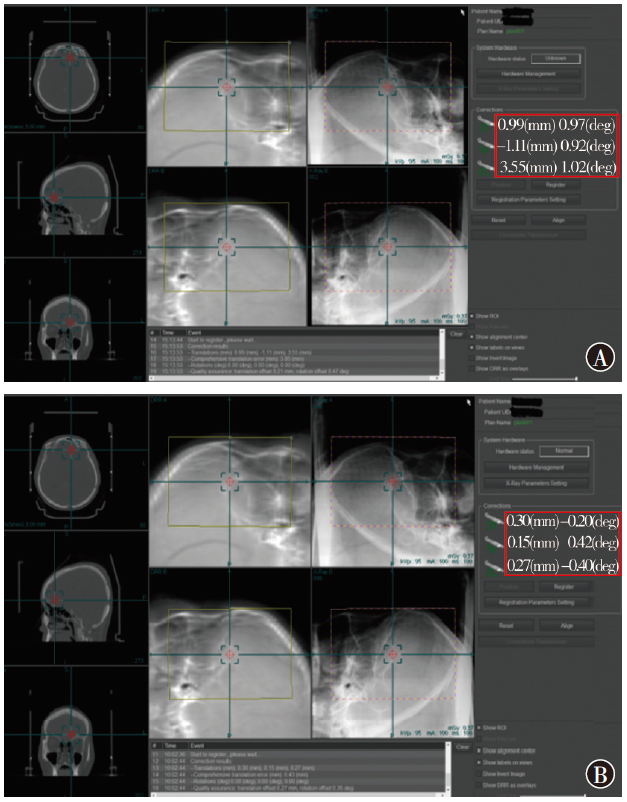

Li Peng, Zhang Shuang, Liu Huafeng, Ji Na, Hou Xiangkun, Xi Aohang, Zong Jianhai. Research on positioning errors analysis of gamma knife pain-free face mask fractionated treatment for head tumors based on kV orthogonal image guidance[J]. Journal of International Oncology, 2025, 52(9): 554-559.